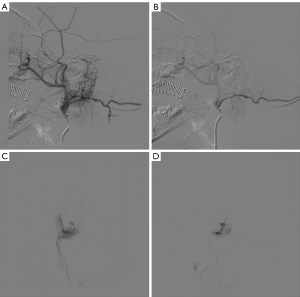

Interventional embolization has been the commonly used treatment of high-flow vascular malformation and the first-line choice for some lesions (6,7,16-18). It can reduce the high-flow blood supply of vascular malformations. Although CM-AVM may demonstrate increased or fast flow by Doppler (5,14,19), there were no reports on the use of interventional embolization therapy. Considering that CM-AVM may lead to impaired physical function, life-threatening bleeding, which is associated with increased morbidity and mortality, and considering the concerns of the patients’ guardians about their appearance and request for treatments, we attempted to perform interventional embolization for pediatric patients with CM-AVMs in the auricular and periauricular area. During the operation of transcatheter arterial embolization (Figure 2), we tried to perform distal embolization as much as possible for that proximal embolization of the feeding artery might be associated with recurrence (20). Due to the lack of experience in CM-AVM embolization treatment, we evaluated the effectiveness of different embolization materials (including pingyangmycin-Lipiodol emulsion, polyvinyl alcohol particles and Gelfoam particles). If the superselective feeding artery angiography showed that the staining of lesion was diffuse, pingyangmycin-Lipiodol emulsion was chosen, because Lipiodol, as a drug carrier, could prolong the retention time of pingyangmycin in the lesion to achieve better therapeutic effect. If only focal staining of lesion was observed on superselective feeding artery angiography, polyvinyl alcohol particles were chosen because they permanently occluded the feeding artery. If normal tissue staining was suspected on superselective feeding artery angiography, gelatin sponge particles were chosen because it is absorbable. The particle sizes of polyvinyl alcohol particles and gelatin sponge particles were selected because too small can easily cause pulmonary embolism, while too large cannot penetrate tiny abnormal blood vessels. All patients experienced a decrease in skin temperature or a lighter redness after treatment. One patient was observed with obvious symptoms rebounding one week after the operation. We suspected that the symptom rebound was due to the small amount of drug used given age and safety restrictions. No significant adverse reactions were observed across the 22 treatments, except for one patient who developed mild skin allergy after one treatment. A high proportion of patients (six patients) were found to have subcutaneous AVMs by DSA, which may be because the high blood flow of arteriovenous malformations leads to more obvious symptoms and thus patients seek medical treatment.